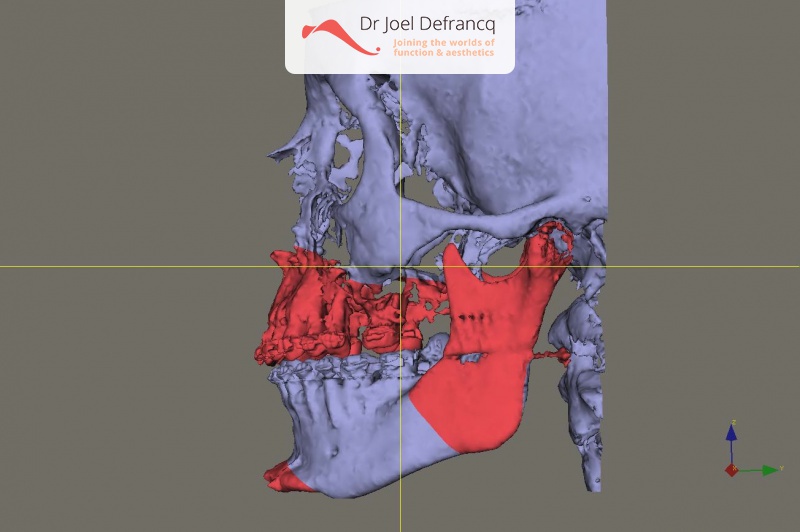

Kaakchirurgie

- Verlenging onderkaak (BSSO)

- Verlenging bovenkaak (Le Fort I)

- Vertikale verlenging bovenkaak (Le Fort I)

- Kinchirurgie

- Redo